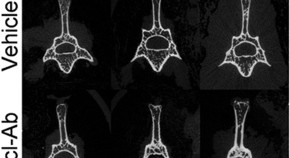

Zhang and colleagues have developed a new targeted delivery system for RNA interference–based bone anabolic therapy. Using dioleoyl trimethylammonium propane (DOTAP)-based cationic liposomes attached to six repetitive sequences of aspartate, serine, serine (AspSerSer)6, the system provided selective enrichment of the encapsulated osteogenic siRNA in osteogenic lineage cells at the bone formation surface and the subsequent depletion of the target gene, encoding the bone formation inhibitor casein kinase-2 interacting protein-1 (PLEKHO1, also known as CKIP-1), leading to the promotion of bone formation in healthy and osteoporotic rats.